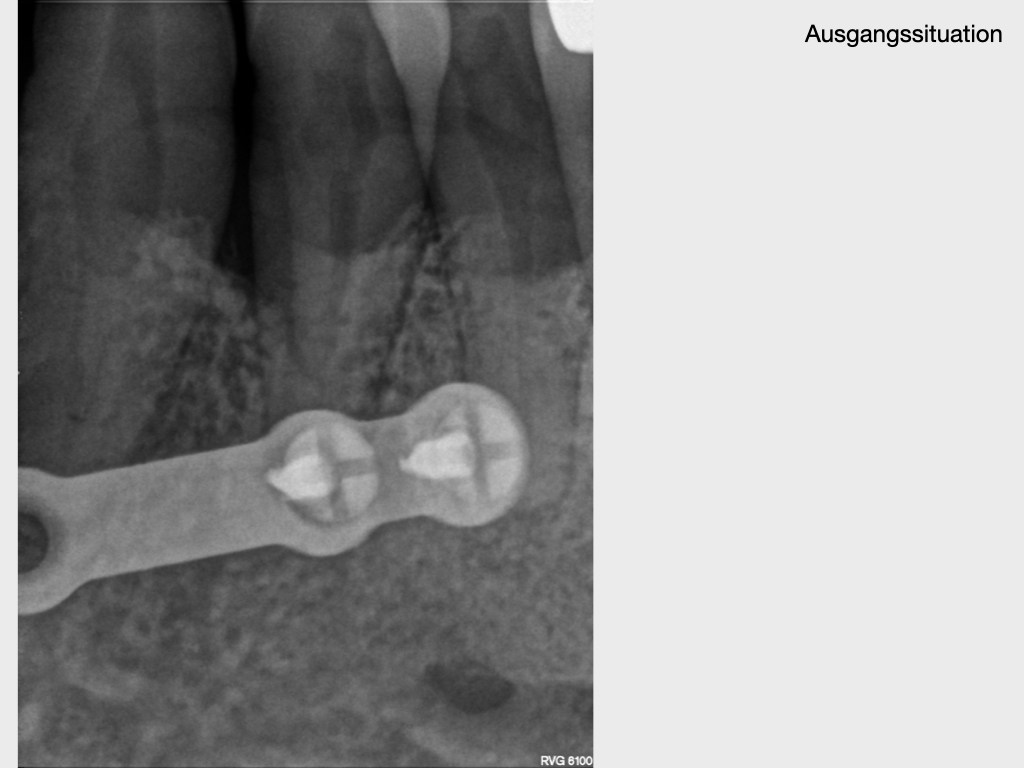

Submuköser Abszess 33